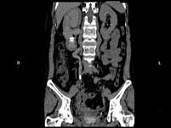

- 多项选择题女,44岁, 突发性胁腹部绞痛并向会阴部放射伴血尿一次,CT扫描如图所示, 下列说法正确的是 ( )

A、右侧肾盂肾盏扩张

B、右输尿管中上段扩张

C、右输尿管内可见沿输尿管走行的高密度影

D、右输尿管结石

E、左肾输尿管未见异常